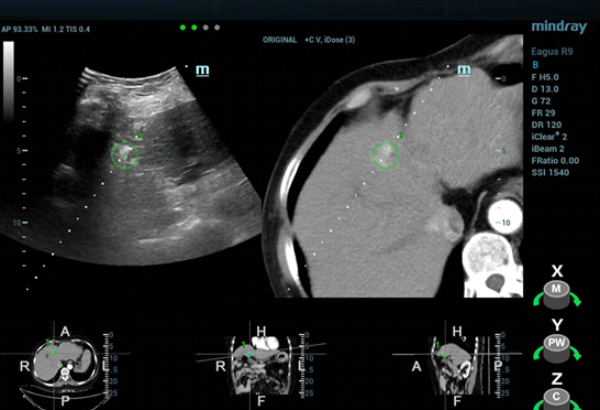

fusion-imaging-fig4

클립 1. 초음파 와 조영제 증강CT 융합 영상.